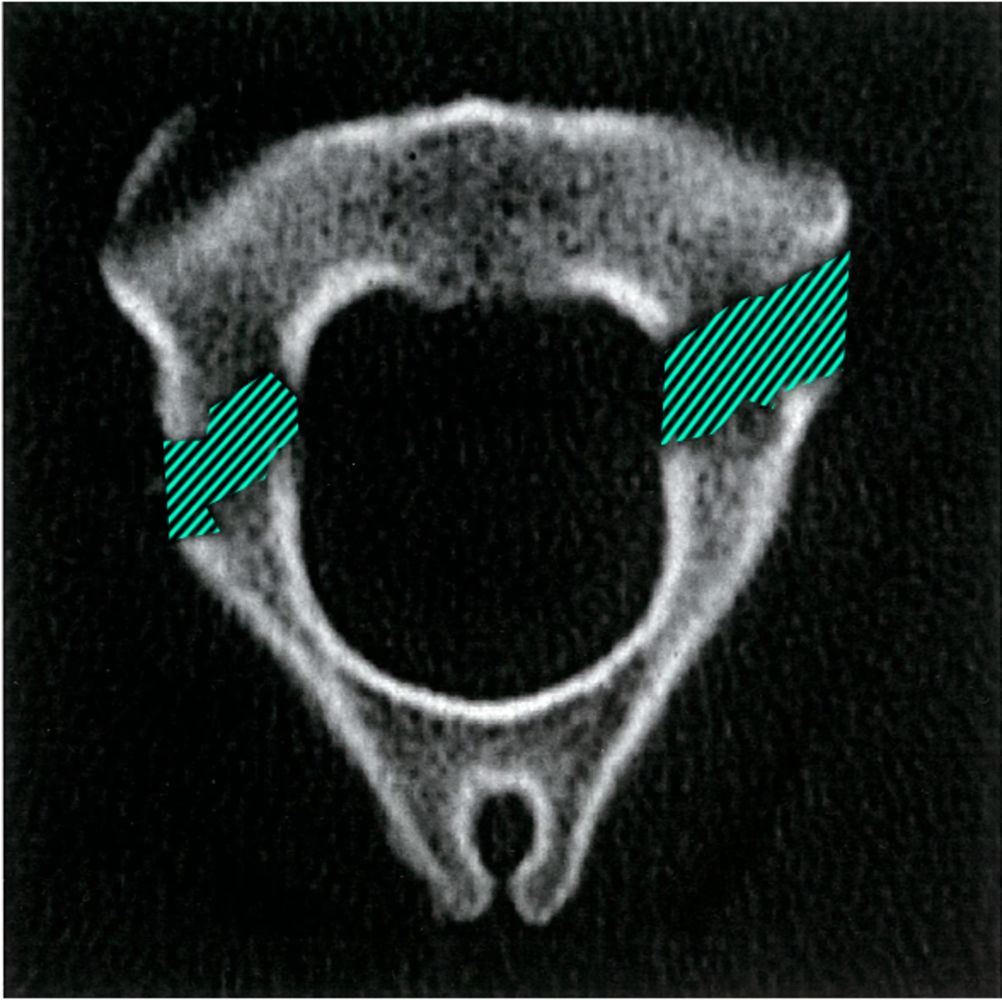

CT appearance of congenital defect resembling the Hangman's fracture, image size:768x1024

CT appearance of congenital defect resembling the Hangman's fracture